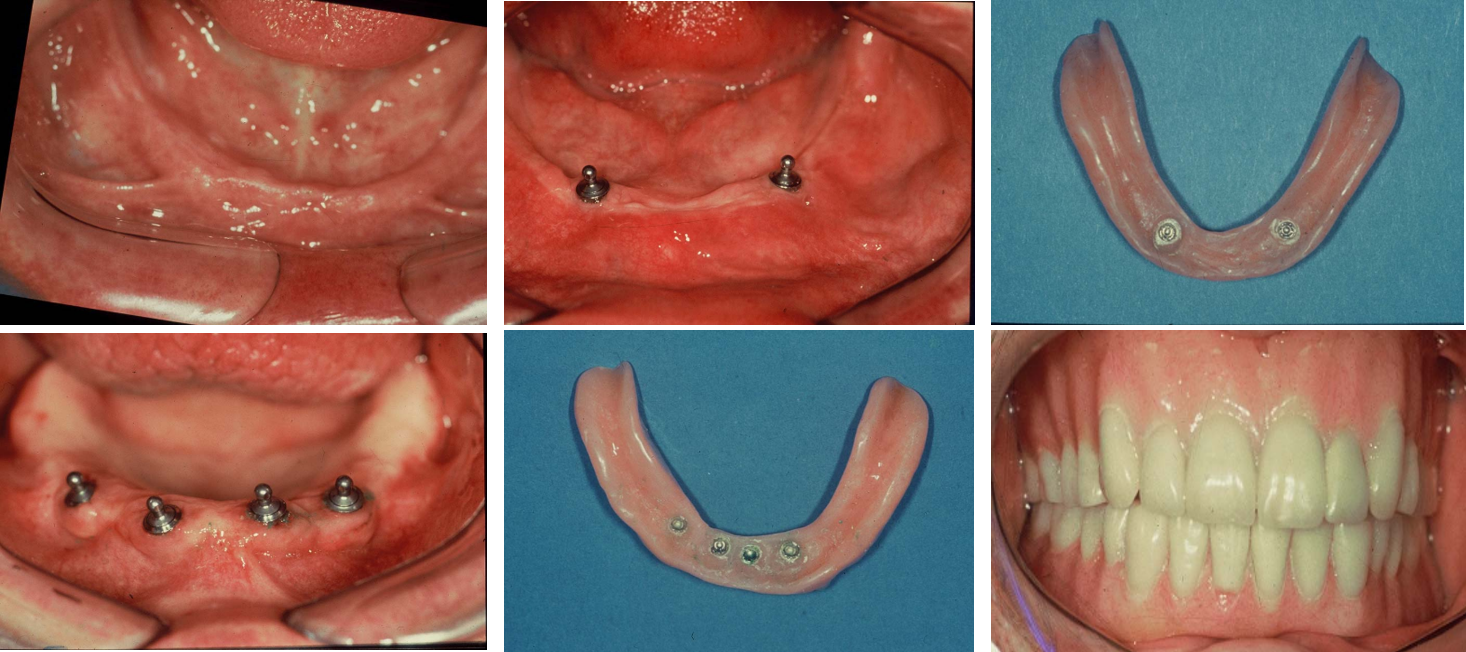

Implant-Retained Overdentures

Oral Health Management for Seniors

Dentures anchored by implants for improved stability in elderly patients

ORAL HEALTH MANAGEMENT FOR SENIORS SEEKING ECONOMICAL SOLUTIONS: A Stable, Cost-Effective Solution

Implant-supported Denture is securely anchored to the jawbone with dental implants, offering enhanced stability compared to traditional dentures that rest on the gums.

Enhanced Stability: Only 2 to 4 implants are typically needed to stabilize a full denture (12-14 teeth), providing a secure fit with significant cost reduction compared to full-mouth fixed _Implants.

Implant-Retained Overdentures Implant Attachments, underside of dentures showing over denture Attachments:  Ball attachments, help to snap a denture into place – Enhanced Stability

IMPLANT-SUPPORTED DENTURES: A STABLE, COST-EFFECTIVE OPTION

Improved Comfort: Eliminates issues like slippage, especially in the lower jaw.

Snap-On Design: Easily removable and reattached for patient convenience, while providing excellent stability and balance, by virtue of the support given by Implants.

Better Balance: Provides superior stability over traditional dentures.

Ideal for Elderly: A secure, non-invasive and comfortable solution for seniors.

Cost-Effective: More affordable than full implants while offering stability.

Comfort for Multiple Missing Teeth: Provides stability and comfort for patients with several missing teeth.

Natural Functionality: Mimics natural teeth, improving biting, chewing, and speaking.

Long-Lasting: A durable, permanent solution compared to traditional dentures.

Gum-Friendly: Reduces gum irritation by resting on implants instead of the gums.

Personalized Care at QDC: Perfect for patients with poorly fitting dentures or those seeking new restorations for enhanced smile aesthetics.